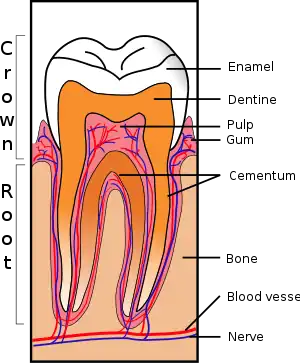

FORLs clinically appear as erosions of the surface of the tooth at the gingival border. They are often covered with calculus or gingival tissue. It is a progressive disease, usually starting with loss of cementum and dentin and leading to penetration of the pulp cavity. Resorption continues up the dentinal tubules into the tooth crown. The enamel is also resorbed or undermined to the point of tooth fracture. Resorbed cementum and dentin is replaced with bone-like tissue.

There are two types of FORL. "Type 1" lesions are focal defects often caused by local inflammation. "Type 2" lesions are characterized by a generalized loss of root radiopacity on a dental radiograph. The definitive cause of type 2 FORLs is unknown, but histologically destruction of the cementum and other mineralized tissue of the tooth root by odontoclasts is seen. It occurs secondary to the loss of the protective covering of the root (the periodontal ligaments) and possibly to a stimulus such as periodontal disease and the release of cytokines, leading to odontoclast migration.[5] However, FORLs can develop in the absence of inflammation.[2] The natural inhibition to root resorption provided by the lining of the root may be altered by increased amounts of Vitamin D, in cats supplied by their diet.[3]